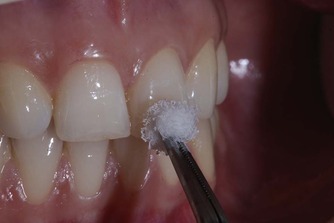

신경치료 전에 꼭 하는 검사

아프다고 다 신경치료를 해야되는게 아닙니다. 신경이 멀쩡해도 아플 수 있습니다. 멀쩡한 신경을 제거하고 싶지는 않으실겁니다. 그렇기 때문에 신경치료 전에는 신경이 살아있나 감염이 되었나 검사를 통해 판단해야 됩니다. 위 사진은 치아에 차가운 자극을 주는 검사입니다. (출처: https://pocketdentistry.com/)

대표적인 검사로는

냉온 자극 검사 (cold test)

전기 치수 검사 (EPT)

타진 검사

치주 검사

등이 있습니다.

이 검사들은

치아 신경이 살아있는지, 염증이 있는지, 이미 괴사했는지

판단하는 데 도움을 줍니다.